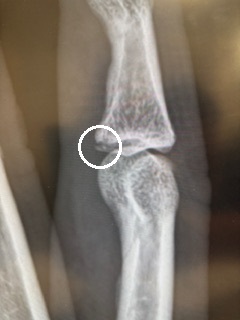

2月に入って早々に、人差し指を骨折してしまいました😂

バレーボールでブロックで跳んだ際、指先にツンと当たった瞬間、「あ゛~~~~!!!」となり…💦腫れがなかなか引かなかったため、4日経って病院へ行くと「折れてますね」とのことでした。

ただ、幸いにもギプスは不要で、アイシング・湿布・テーピングで固定しながら様子を見ることになり、「2週間後にまた来てください」と言われました。